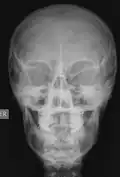

Las imágenes digitales que se adquieren hoy en día, ya sea en radiología digital indirecta (CR) o directa (DR), presentan una gran ventaja debido a la potencialidad que su manejo informático ofrece, en el cual es posible sobre la base de una imagen adquirida aplicar diferentes herramientas como filtros que permiten mejorar el realce de los bordes, suavizar, analizar el histograma y realizar análisis de la calidad de la imagen obtenida. Estas herramientas están disponibles en las consolas de procesado de imágenes de los equipos radiológicos, pero también existen programas dedicados como ImageJ que permiten realizar el análisis de las imágenes, ya sean de uso médico o no. Una de las funcionalidades de ImageJ es la posibilidad de "retocar" la imagen aplicando filtros como los que se observan en las siguientes imágenes en las cuales hemos aplicado a la imagen base de una radiografía de cráneo (al centro) un filtro que permite suavizar la imagen (Imagen 1) y luego a la misma imagen le hemos aplicado un filtro de reforzamiento de los bordes (Imagen 2).

-

Imagen 1 -

Imagen 2 -

Imagen basal